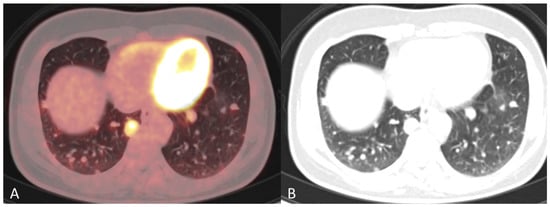

Figure 2. (A) Baseline axial PET/CT fused image. The metabolic activity is inhomogeneous, with areas of high to low metabolic activity. (B) Contrast-enhanced axial CT shows an enlarged uterus with endometrial thickening and polypoid tumour masses protruding into the uterine cavity. The tumor appears hypodense to the myometrium with signs of myometrial invasion. There was no involvement of the ovaries, fallopian tubes or cervix on either the PET or CT.

Figure 3. (A) Baseline axial PET/CT fused and (B) axial CT shows a small metabolic active hyperdense tumour located in the left vaginal corner, verified by biopsy as representing a metastasis from endometrial hepatoid adenocarcinoma ((B), arrow).